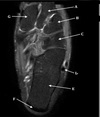

5

Perfectly

12

Q

What is letter B?

A

BICEPS TENDON (LONG HEAD)

How well did you know this?

1

Not at all

2

3

14

What is letter D?

POSTERIOR LABRUM